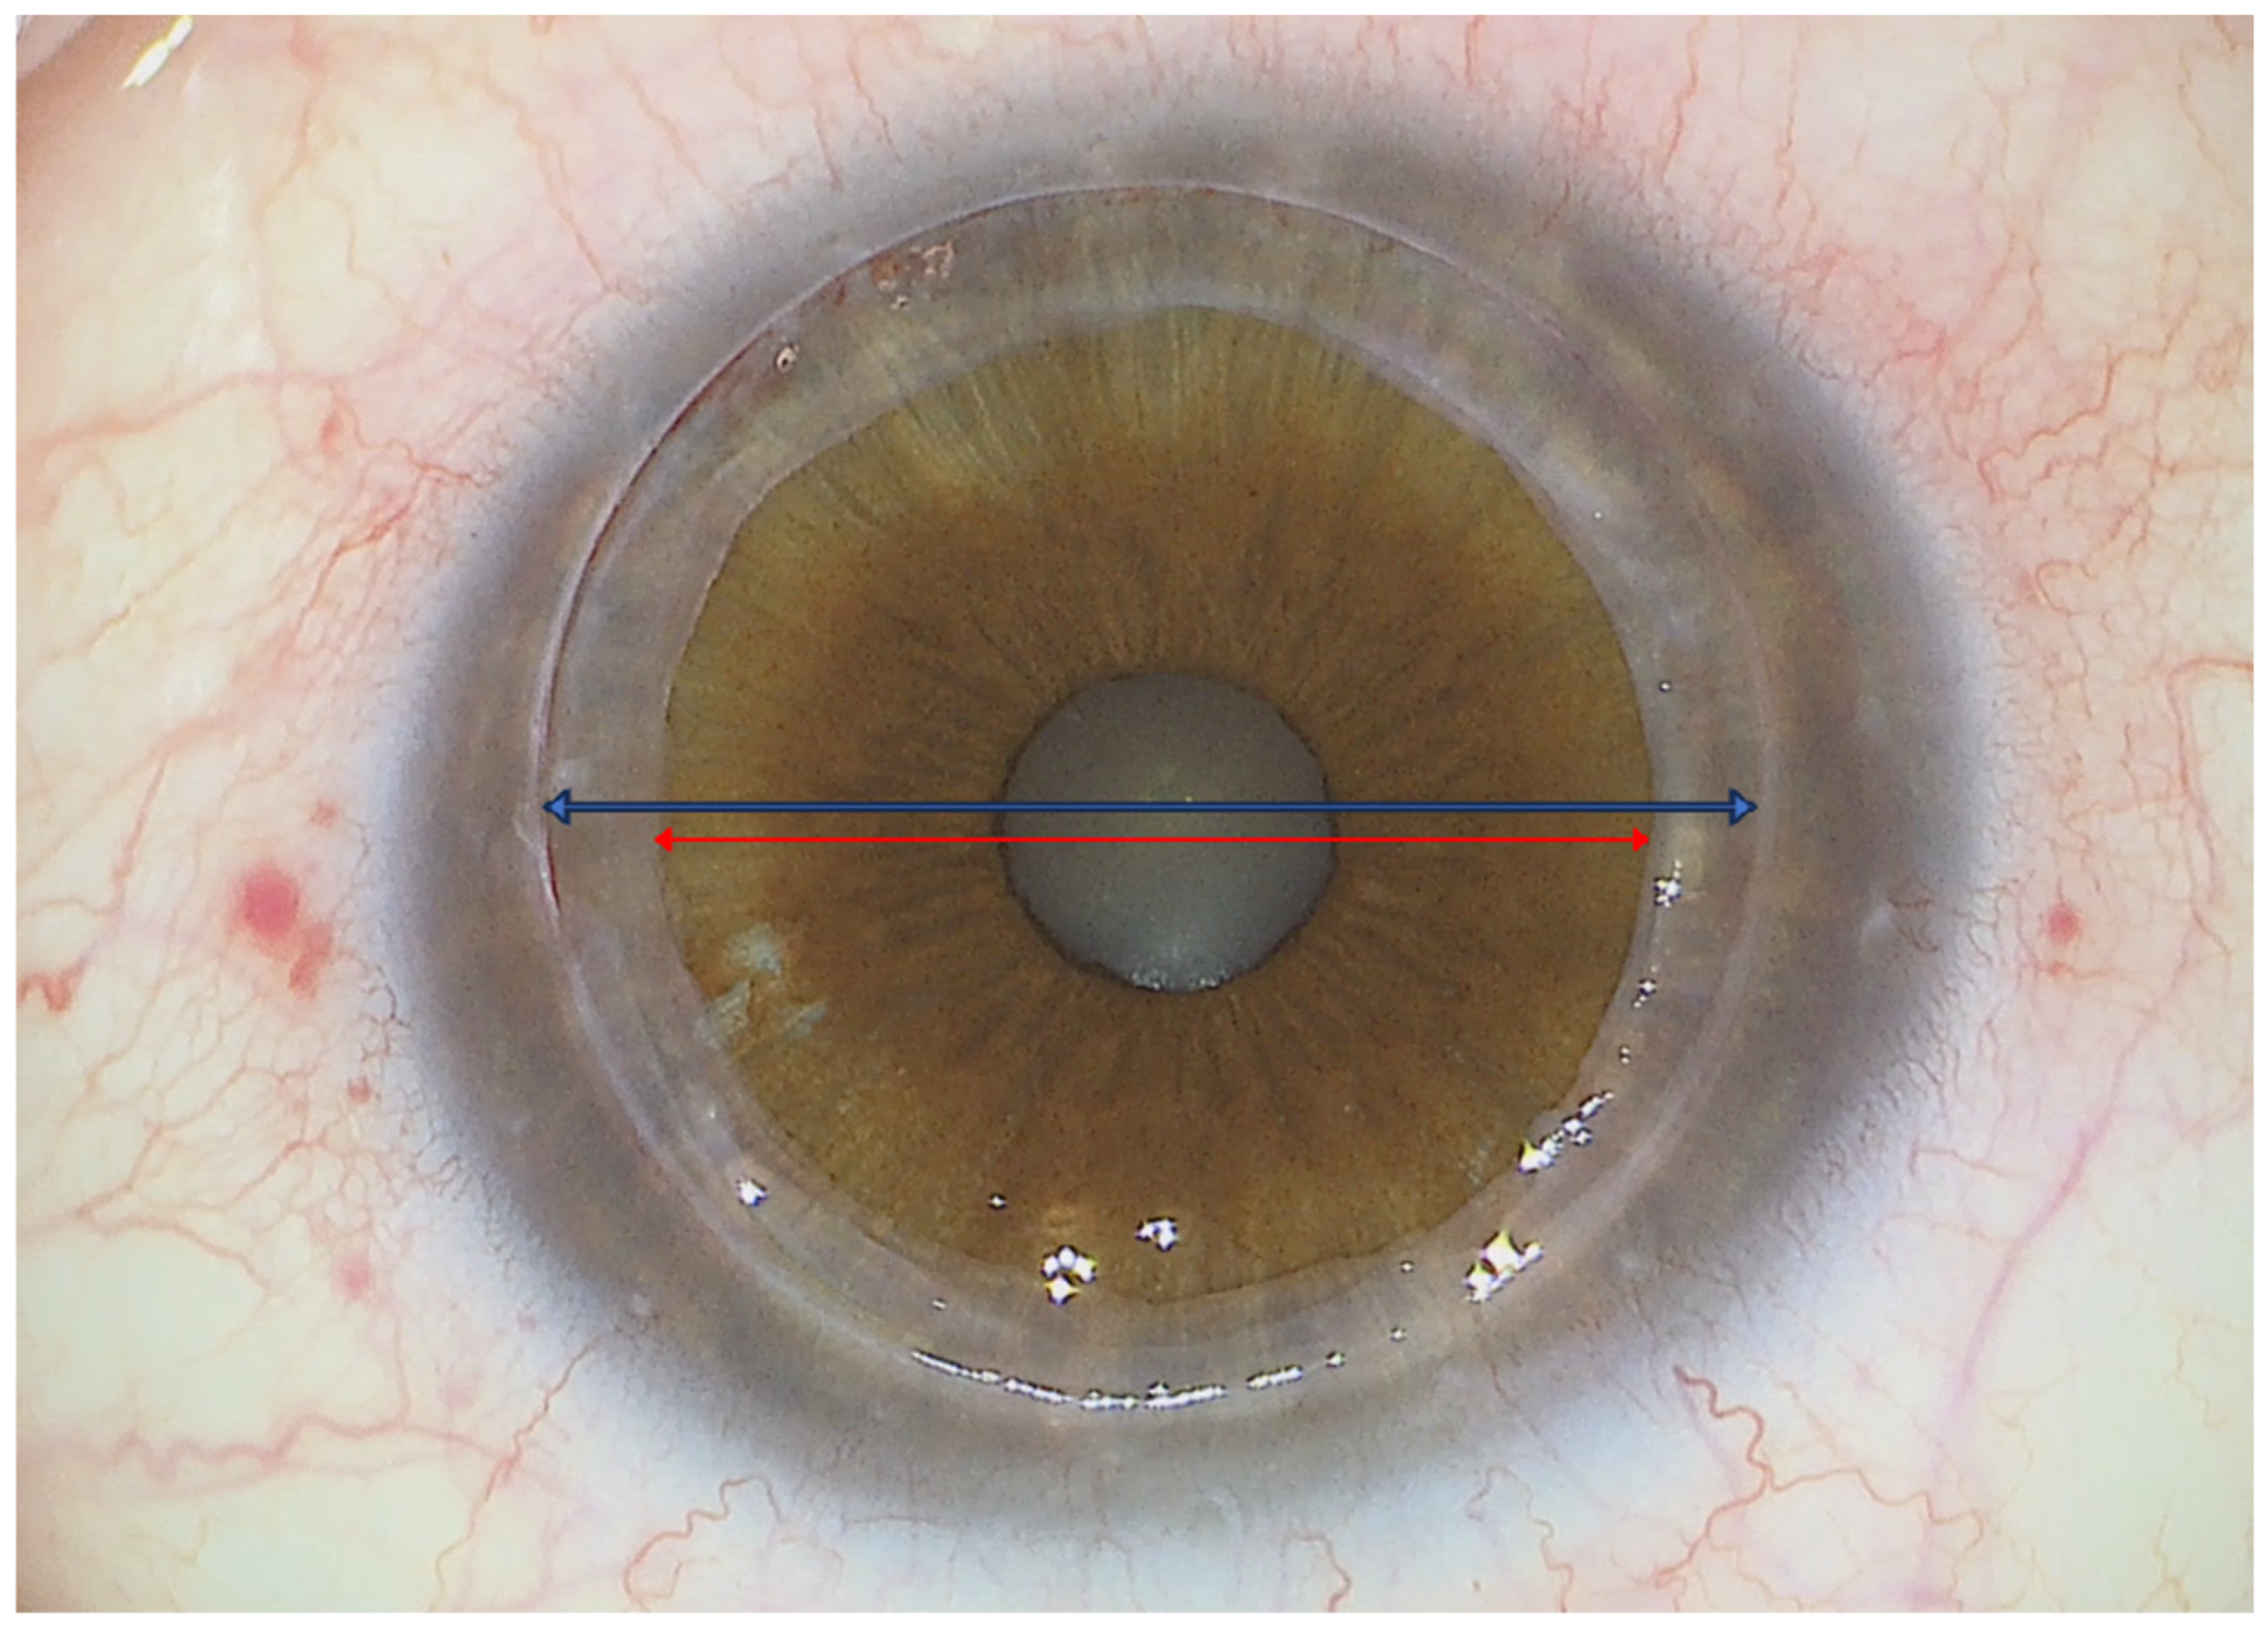

3.4. Graft Positioning and End of the Procedure

4. Results